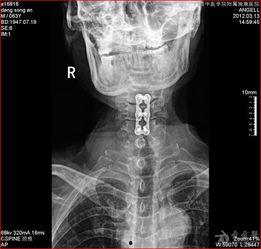

在医疗领域,x光透视频可是大显身手。医生们可以通过它来观察患者的骨骼、内脏等部位,从而做出准确的诊断。比如,骨折、肿瘤等疾病,通过x光透视频就能一目了然。